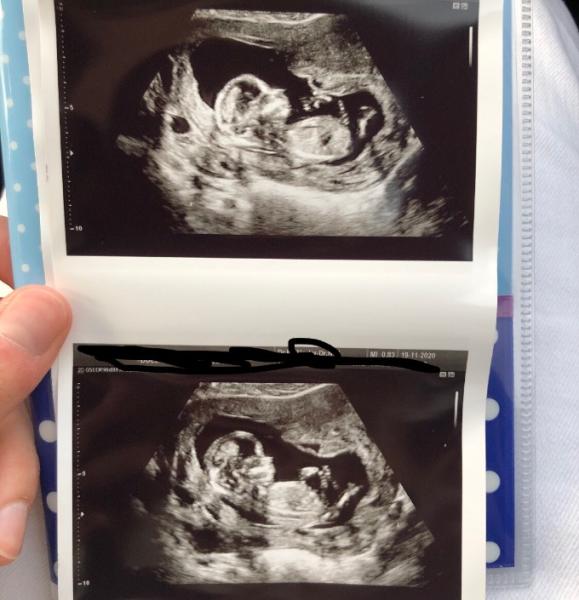

Oh wow das is ja mal echt gut. Ich zeig dir mal mein Bild von der 13ten Woche. Was würdest du dazu sagen ? Ich weiß ja mittlerweile das es doch kein Mädchen wird

Bild zu

Hallo, also bei dir finde ich es sehr schwer. Falls das auf dem Bild wirklich der Nub sein sollte, würde ich vom Winkel her auf einen Jungen tippen, aber irgendwie sieht es so geteilt aus, was ja eher für Mädchen sprechen würde. Live beim Ultraschall ist es daher manchmal sogar besser zu sehen. In welcher Woche bist du jetzt und wann hast du dann erfahren, dass es ein Junge wird? LG